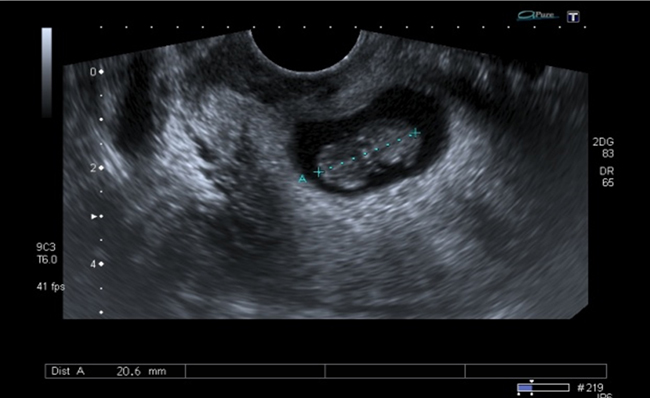

A la paciente se le realizó una prueba en sangre para cuantificar la fracción beta de la gonadotrofina coriónica humana (Abbott Laboratories. Architect.B-hCG Total), que se reportó en 31.819 mUI/ml. También se le tomó una ecografía endovaginal (Toshiba-Xario XG) que mostró la presencia de útero con medidas de 72 × 52 × 54 mm con un cuello de 35 mm con orificio interno cerrado. El endometrio midió 18 mm, sin evidencia de saco gestacional intrauterino y en la región ístmica y cervical, por debajo de las arterias uterinas, se encontró un saco gestacional de 30 mm con presencia de embrión único de 20,6 mm sin presencia de actividad cardiaca fetal (figuras 1 a 4).